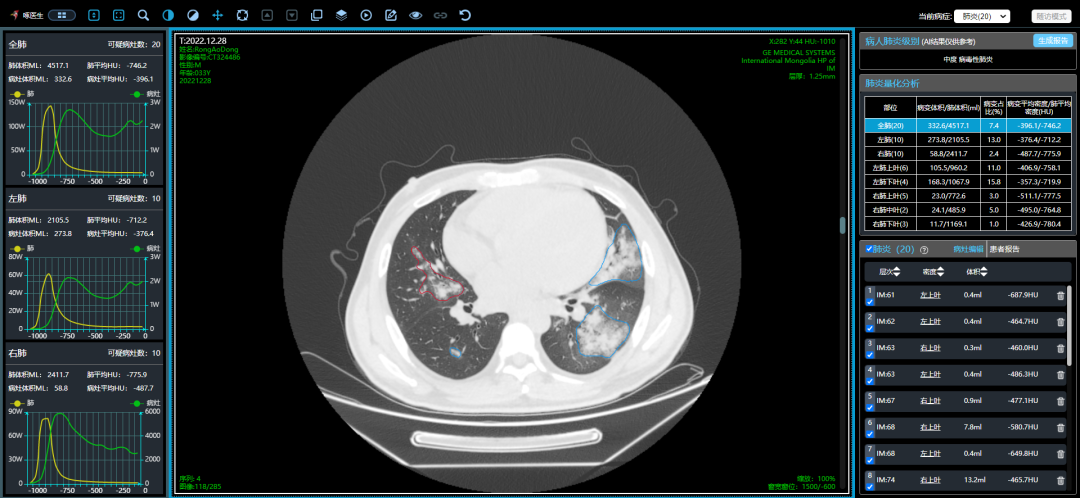

案例三,30歲,男性,確診病例

胸片顯示雙肺彌漫性病變

影像所見:發(fā)熱12天,胸悶、氣喘7天。胸部CT顯示兩肺彌散性磨玻璃影,呈“白肺”改變,其內(nèi)可見空氣支氣管征、雙側(cè)膈面上抬。

從這3個確診新冠肺炎呈“白肺”病例來看,“白肺”多見于老人、兒童以及帶有基礎(chǔ)病的新冠患者,病灶可發(fā)生在肺內(nèi)任何肺葉,病灶形態(tài)特點(diǎn)也是多樣化,符合病毒性肺炎的影像表現(xiàn)。從影像學(xué)角度出發(fā)重點(diǎn)在于快速評估病情,提升人工讀片的客觀性。 “啄醫(yī)生閱片機(jī)器人??新冠肺炎CT影像輔助分診與評估系統(tǒng)”可以準(zhǔn)確地識別新冠肺炎的典型影像表現(xiàn)如雙肺外周胸膜下多發(fā)的磨玻璃影、小葉間隔增厚或合并鋪路石征等,對于部分患者由于影像表現(xiàn)早于臨床癥狀,更具有早期發(fā)現(xiàn)、早期診斷的優(yōu)勢。